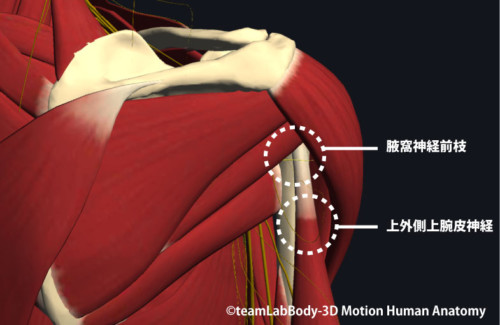

⑤ 腋窩神経障害(四角間隙症候群など)

機序・所見

腋窩神経は四角間隙(小円筋・大円筋・上腕三頭筋長頭・上腕骨)を通過。圧迫で三角筋・小円筋の筋力低下+肩外側の知覚低下。

四角間隙を構成する筋(大円・小円・肩甲下・長頭)の緊張軽減、姿勢・過頭動作の量コントロール。神経症状が強い/遷延例は医療受診。